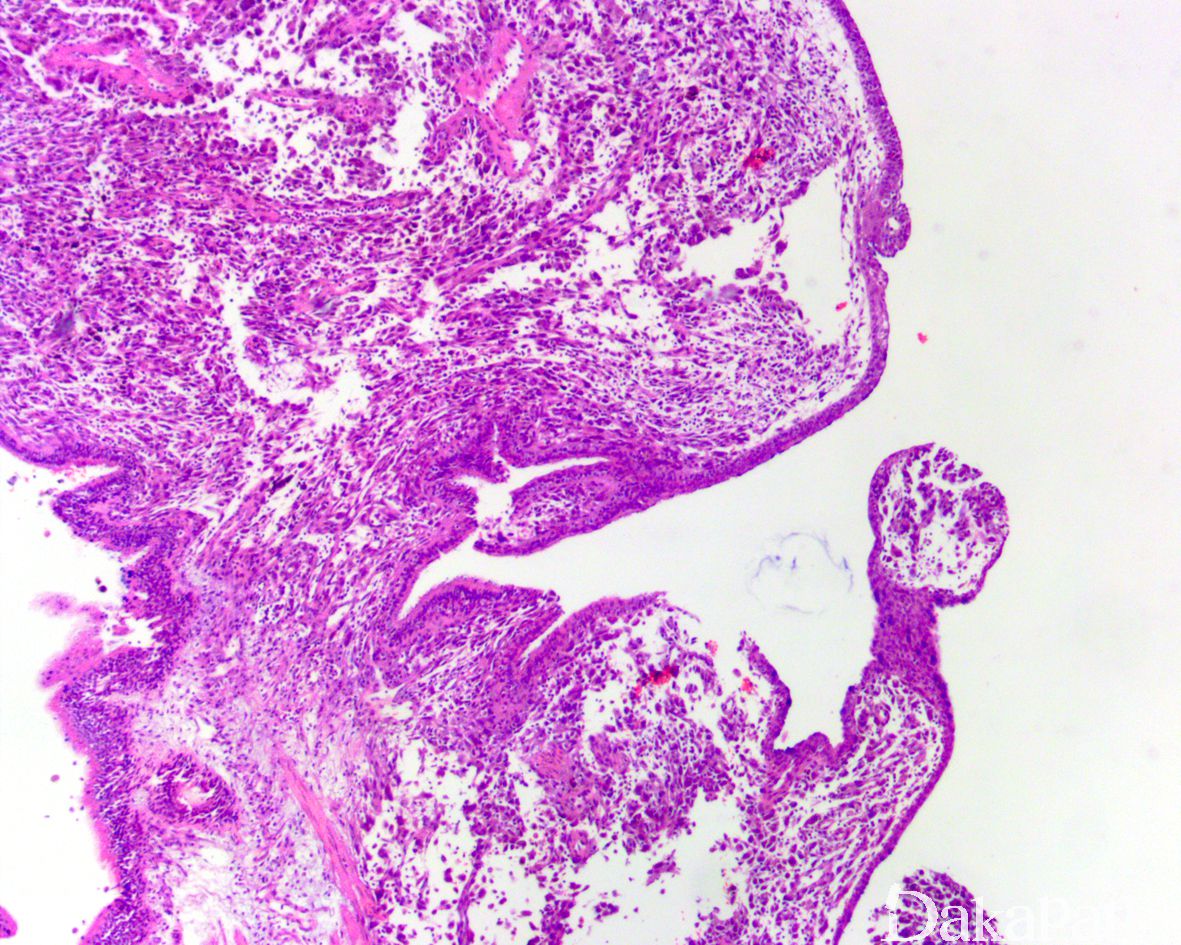

镜下表现为多发性的囊性扩张的气道,囊壁的间隔厚薄不均匀,被覆立方形呼吸性上皮或伴鳞状化生,上皮下为富于细胞的纤维母细胞样细胞增生,呈席纹状或交错束状排列,部分区域亦可见完全呈实性增生的病变,瘤细胞具有较丰富的嗜酸性胞浆,核形态较温和,核分裂象罕见,间质内可见淋巴细胞、组织细胞和嗜酸性粒细胞浸润以及含铁血黄色沉积,局灶可见黏液变性;

3。囊腔内可见泡沫细胞聚集、胆固醇裂隙形成,周围肺泡组织常见出血改变。